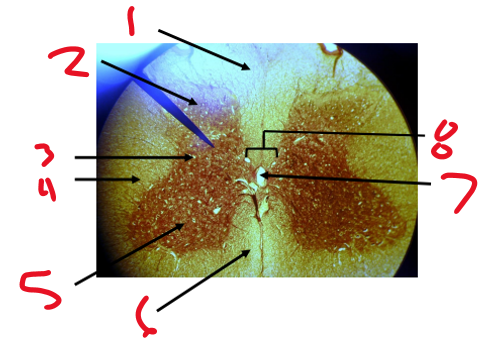

Name structure 1

Dorsal funiculus

Name structure 2

Dorsal horn

Name structure 3

Lateral horn

Name structure 4

Lateral funiculus

Name structure 5

Ventral horn

Name structure 6

Ventral funiculus

Name structure 7

Central canal

Name structure 8

Gray commissure